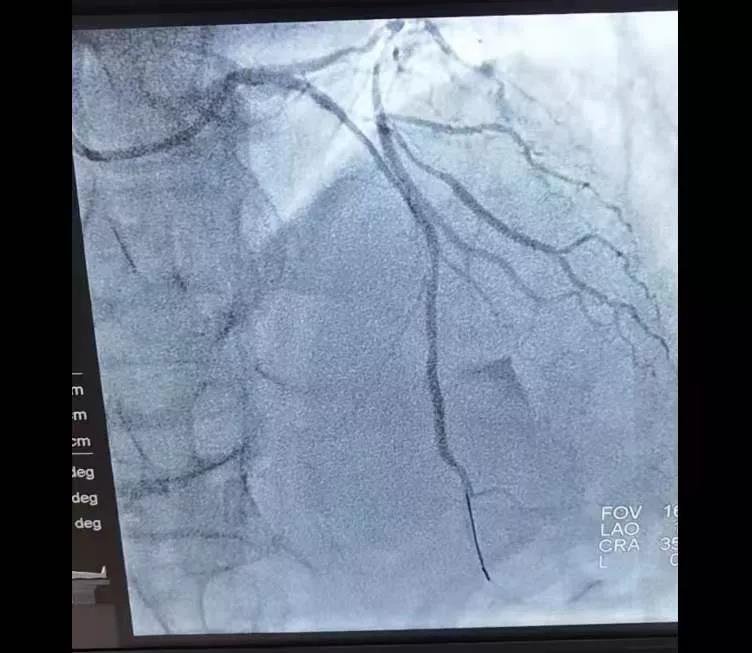

9点52分患者到达医院,双绕直接进入导管室,手术人员立即开始手术,于10点21分开通闭塞的冠状动脉,恢复血流,大家争分夺秒,把握“黄金90分钟的救治时间”,成功挽救了患者生命。